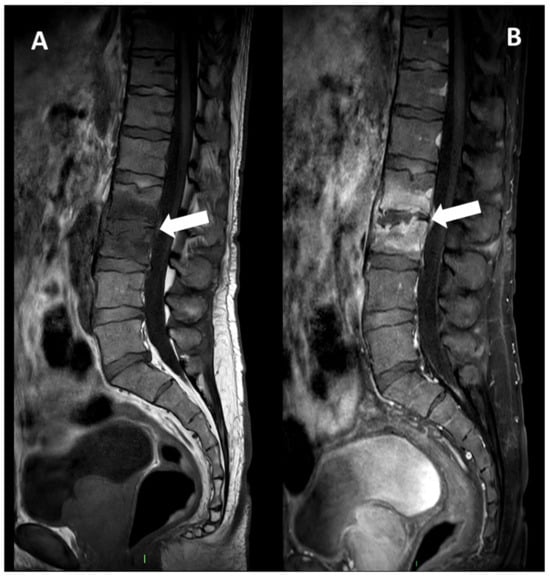

Figure 7. A 73-year-old male presented with a rapidly evolving lumbar pain and fever, with an inflammatory syndrome on blood samples. A first MRI was performed as infectious spondylodiscitis was suspected, which included (A) STIR T2-weighted imaging (WI) and (B) fat sat T1-WI after gadolinium chelates injection. It shows a high signal intensity (SI) of the L3-L4 disc while other disks are in lower signal (black arrowhead), as well as linear subchondral contrast enhancement (CE) of the L3-L4 endplates both linear and more pronounced at the upper anterior corner of the L4 vertebral body (white arrowheads). Moreover, the left T11-T12 facet joints displayed marked edema of the subchondral bone and surrounding tissues (white arrows). A control MRI with SITR T2-WI (C) and fat-suppressed CE-T1-WI (D) was performed one month later, demonstrating a marked narrowing of the L3-L4 disk (black arrowhead), erosions of the vertebral body (dashed white arrows), extensive edema in the L3 and L4 vertebral body (white arrowhead), a persisting arthritis involving the left T1-T12 facet joint. Bacillus cereus was found on the Bacterial analysis of the L3-L4 disk biopsy.